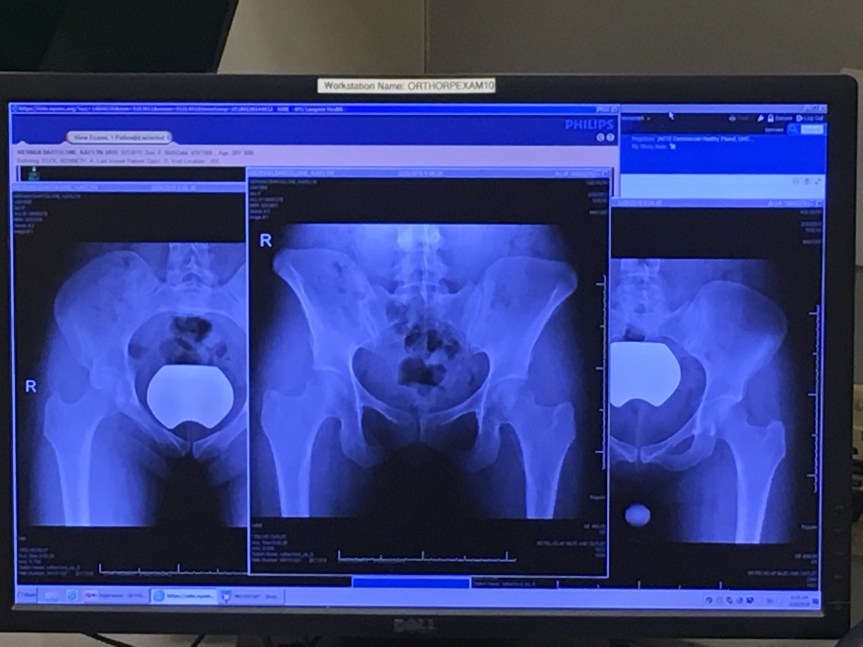

You CAN Recover From A Pelvic Stress Fracture In 3 Months

When I was diagnosed with a pelvic stress fracture in February, I was devastated. I was just about to begin training for my first marathon in two years after dealing with a nasty calf strain for half of 2017. And the prognosis, at least according to the Internet, was grim. My injury, to be exact, … Continue reading You CAN Recover From A Pelvic Stress Fracture In 3 Months

Pubic Ramus Stress Fracture, An Update

Not exercising doesn’t make for very interesting blogging, but I’m overdue for an update. I was kind of hoping that if I waited a bit long, I could come to you with news of a triumphant return. Alas. In my first post about my most recent injury, I laid out what led up to my … Continue reading Pubic Ramus Stress Fracture, An Update

Back on the Injury Train: Pubic Ramus Stress Fracture

Buckle in guys, this is a long one because the injury train is leaving the station and we’re on it. I really do have the worst luck, because not only do I end up injured often, but I end up with some unusual injuries. This time around it is a stress fracture of the pubic … Continue reading Back on the Injury Train: Pubic Ramus Stress Fracture